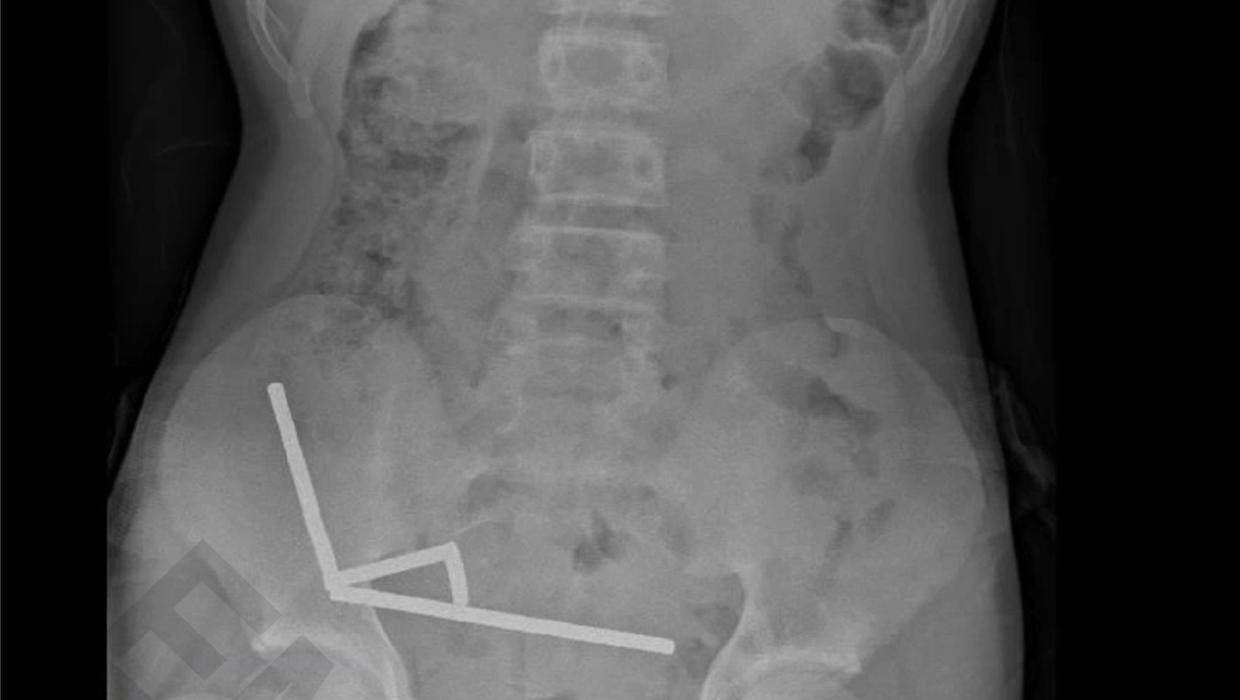

A 13-year-old boy was hospitalized at Tauranga Hospital in New Zealand after swallowing up to 100 small magnets. The incident necessitated urgent medical intervention, resulting in a significant surgical procedure that included the removal of part of his bowel.

Medical professionals emphasize that ingesting magnets poses serious health risks, particularly when multiple magnets are involved. When magnets are swallowed, they can attract each other through intestinal walls, leading to blockages and potential perforations. In this case, the boy’s condition required a comprehensive surgical approach to prevent further complications.

Dr. David Smith, the lead surgeon, stated, “This type of injury can lead to life-threatening conditions if not addressed promptly.” According to hospital sources, the boy’s surgery took place on December 5, 2023, and lasted several hours. The medical team successfully removed the magnets and repaired the damaged sections of the bowel.